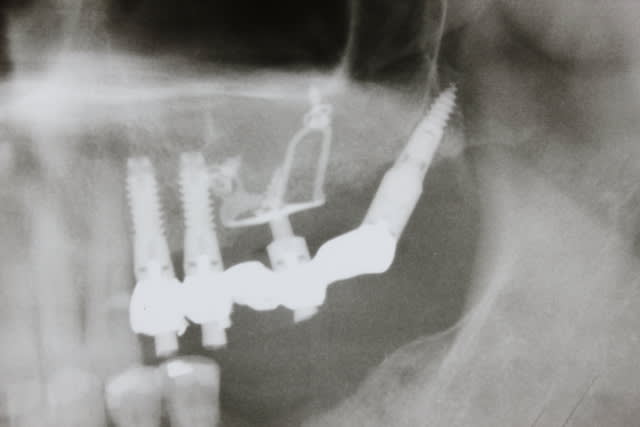

Patient d un pote chez qui on a pris l option décrite

1. poser les 4 cylindres des Pm

2. attendre 3 mois intégration des 4 cylindres

3. poser les plaques et les deux petits ptérygos avec MCI/MCD

Je vous rassure on a depuis posé en bas 6 cylindres pour remplacer les 6 et 7